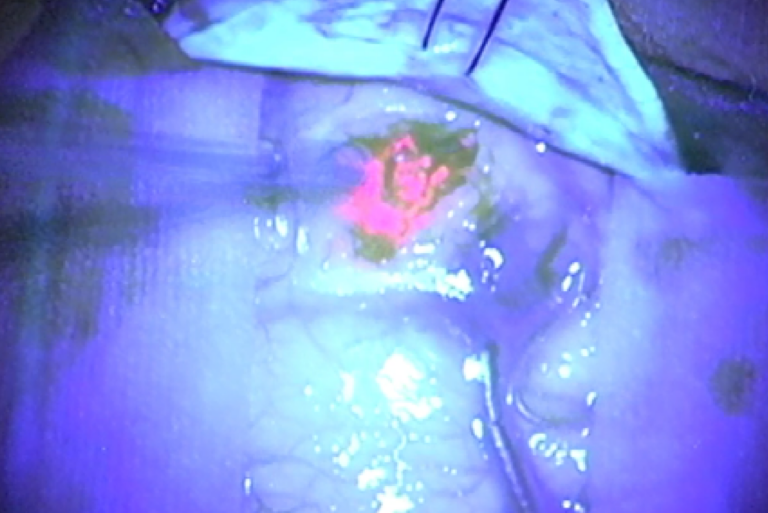

Fluorescent Staining: This technique involves the use of fluorescent dyes, such as 5-aminolevulinic acid (5-ALA), which are absorbed by tumor cells and cause them to fluoresce under certain light conditions. 5-ALA is particularly useful in glioma surgeries, as it accumulates in tumor cells and allows surgeons to distinguish malignant tissue from surrounding healthy brain matter.